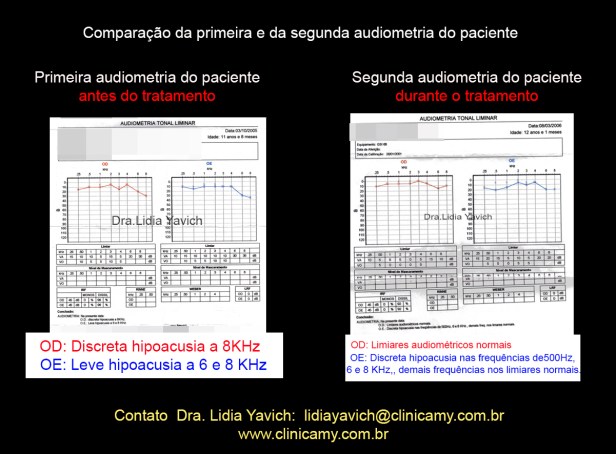

Uma audiometria é produzida usando uma medida relativa da audição do paciente, em comparação com um valor estabelecido “normal”. É uma representação gráfica das respostas limiares auditivas que são obtidas a partir de testes de audição no paciente através de estímulos de tons puros. Os parâmetros da audiometria são frequência, medida em ciclos por segundo Hertz (Hz) e intensidade, medida em decibéis (dB).

A primeira audiometria do paciente revela uma discreta hipoacusia no ouvido esquerdo e uma leve hipoacusia no ouvido direito.

A segunda audiometria do paciente revela limiares normais no ouvido esquerdo e uma discreta hipoacusia no ouvido direito.

Comparação da primeira e a segunda audiometria do paciente durante o tratamento.

Normalização dos limiares no ouvido direito e melhora nos limiares do ouvido esquerdo.